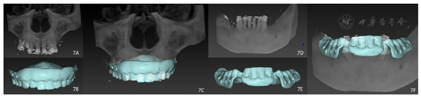

治疗过程:(1)术前准备:①藻酸盐取初印模,制作个性化托盘(图4);②用个性化托盘取硅橡胶终印模,灌制终模型;③制作光固化树脂

托及蜡堤(图5),面部比例二等分法确定垂直距离,肌肉疲劳法及吞咽咬合法确定水平关系,面弓转移患者颌位关系,上

架;④排牙,制作放射导板(图6A);⑤试戴放射导板(图6B~D),拍摄两次CBCT(患者佩戴放射导板拍摄CBCT以及放射导板单独拍摄CBCT)。(2)方案设计:①将两次CBCT获取的DICOM数据导入种植设计软件重叠(图7),以修复为导向指导上下颌种植体位置摆放(图8、图9);②生成并打印手术导板(图10)。(3)利用手术导板和导板锁,翻制模型,制作临时修复体(图11)。(4)一期手术过程:铺巾消毒,局麻后拔除上下颌余留牙,搔刮拔牙窝内炎性肉芽组织,于34-36、44-46区牙槽嵴顶近远中向切开牙龈,翻瓣。就位并固定手术导板,于11、13、16、22、25、26、32、34、36、42、44、46定点,按术前设计方案植入NobelParallelTM ConicalConnection种植体。除26区种植体外,其余种植体初期稳定性均达到35N.cm以上,就位复合基台,戴入保护帽,修整牙龈黏膜,缝合牙龈(图12A~F)。术后拍摄全景片(图13)。次日复诊,取下保护帽,戴入预制的临时修复体,调合(图12G)。